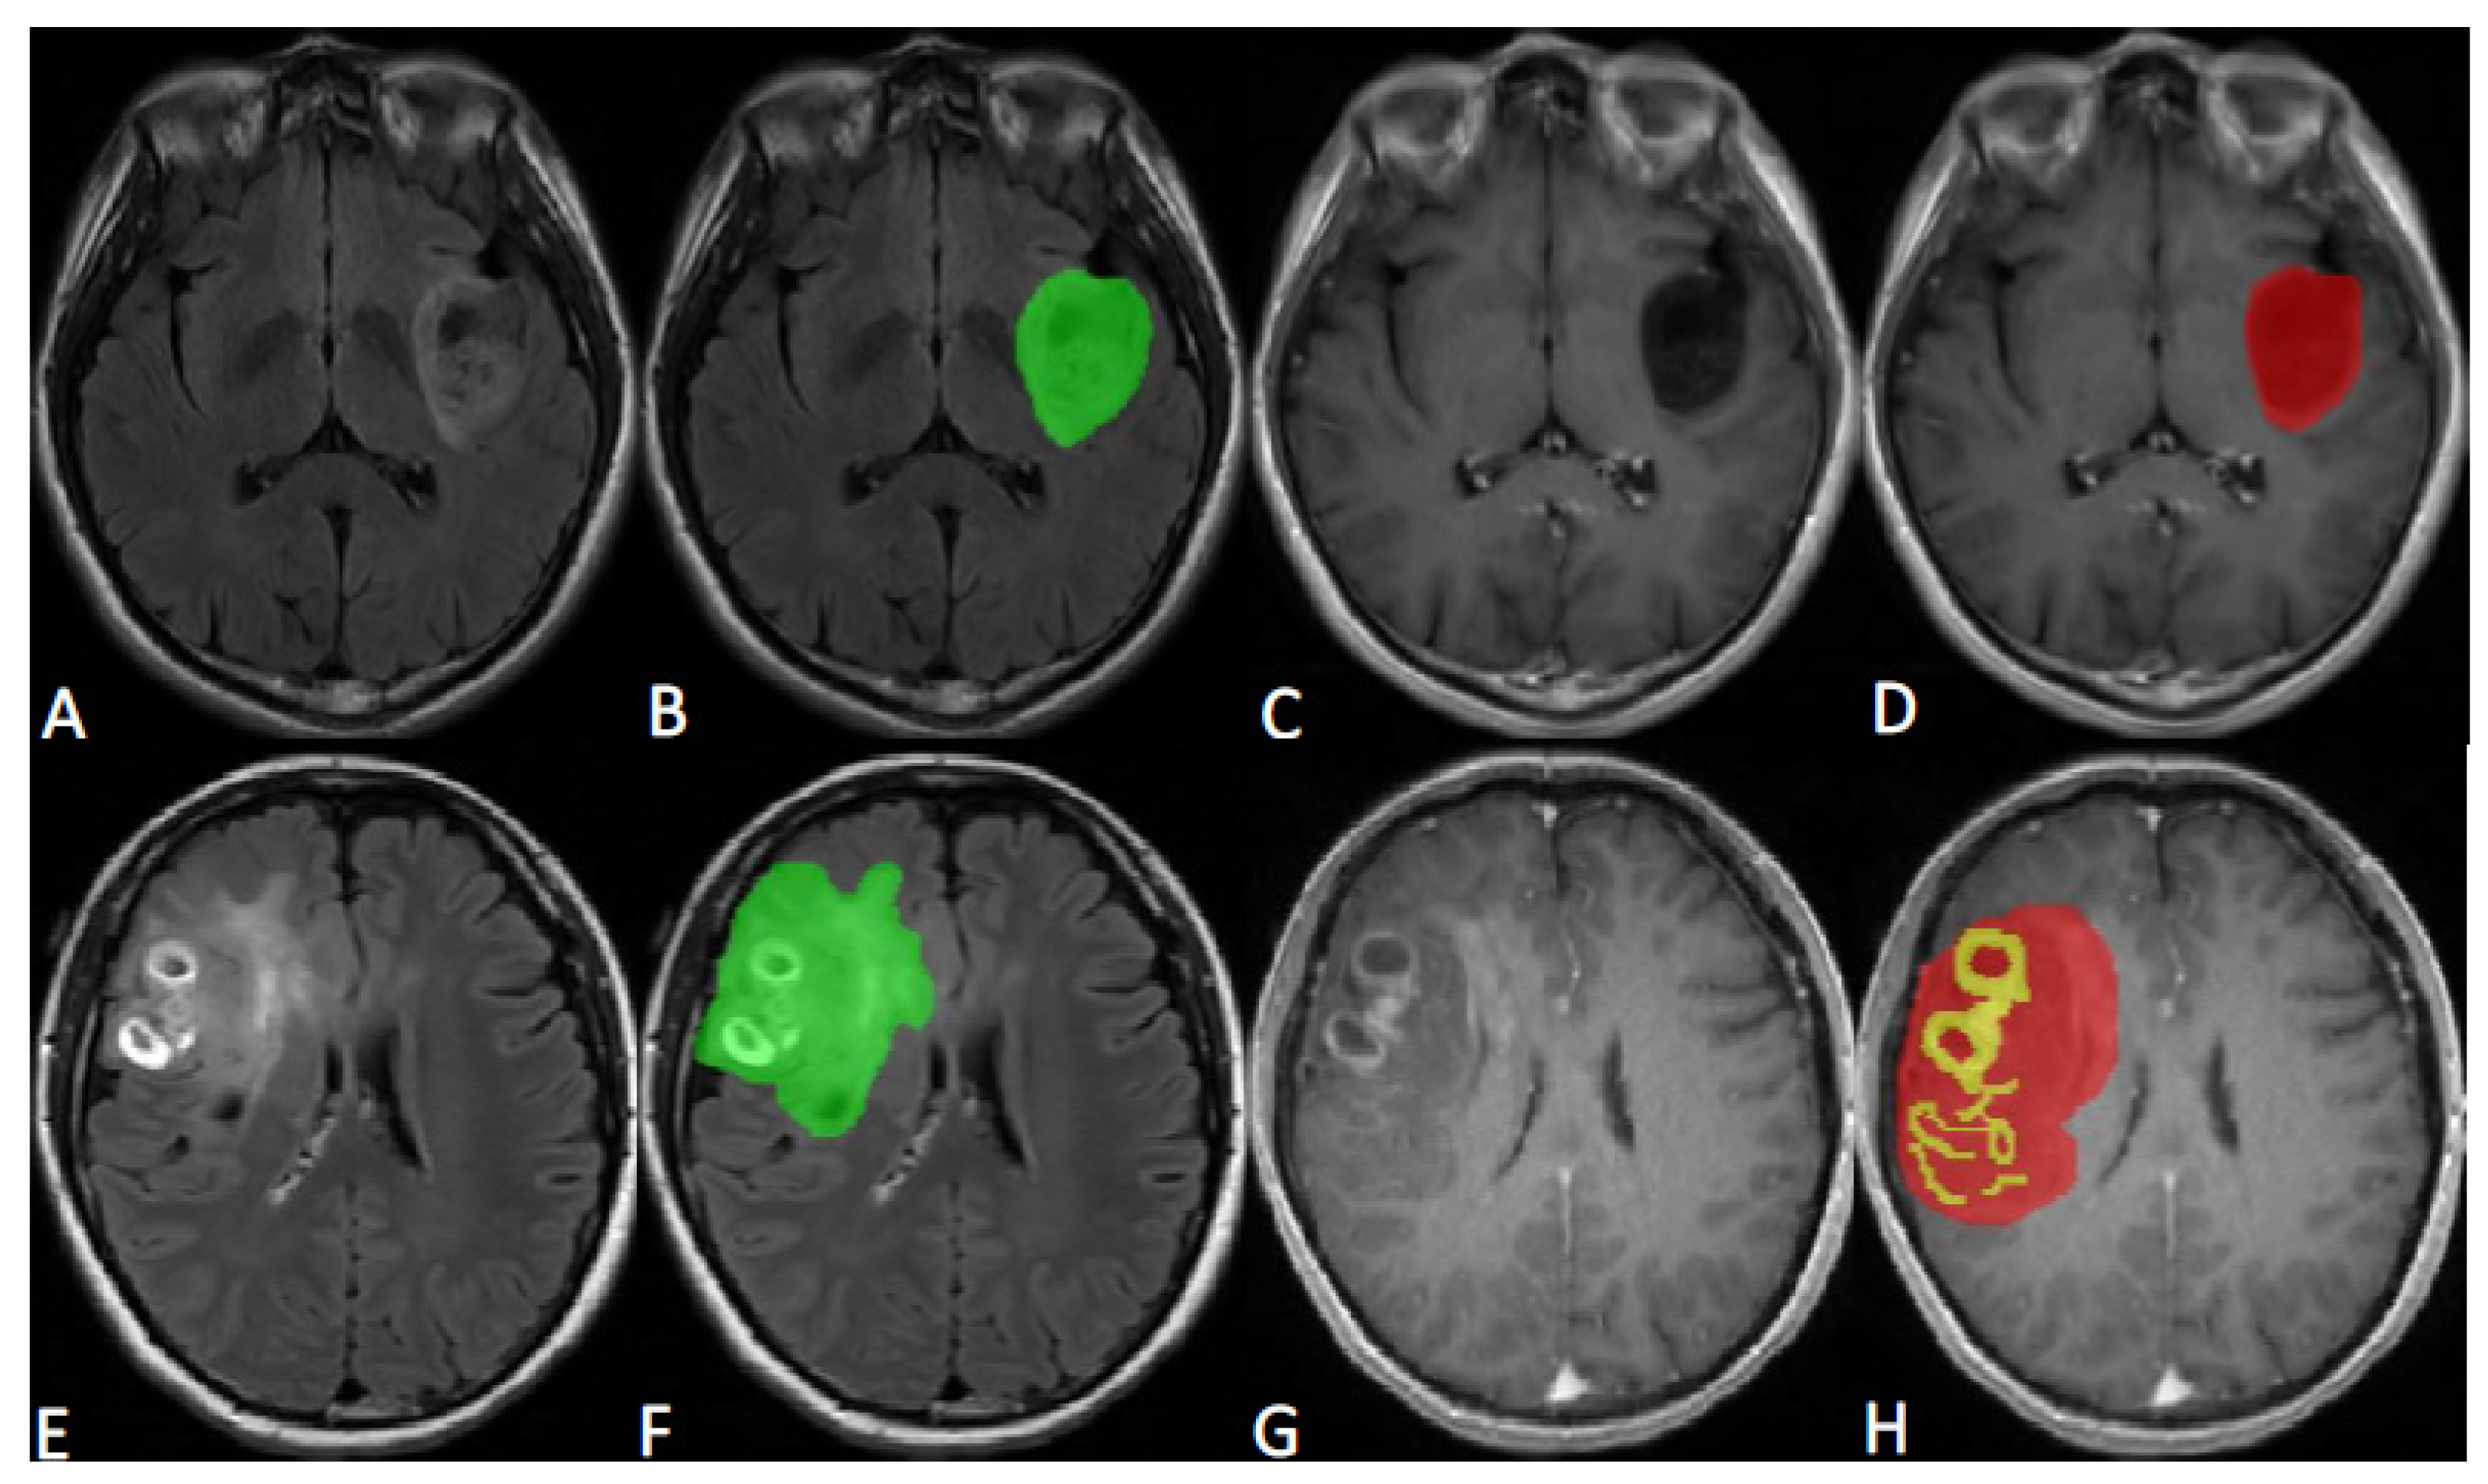

MRI image segmentation was based on the research of Zacharaki et al. [22] and the Multimodal Brain Tumor Image Segmentation Benchmark [23], and it was implemented by a radiologist with more than 20 years of experience in neuro-oncology radiology. The tumors were segmented on T2-FLAIR and CE-T1WI axial images using ITK-SNAP [24] (version 4.0.0, PICSL, Philadelphia, PA, USA, http://www.itksnap.org/pmwiki/pmwiki.php, accessed on 26 April 2023). All tumors were delineated into two parts, called ROI1 and ROI2. ROI1 represents the maximum anomaly region (MAR), and it was delineated on T2-FLAIR image and was represented in green; ROI2 represents the tumor area (tumor), and it was delineated on CE-T1WI image, with yellow representing the enhancement area and red representing the nonenhancement area. The maximum anomaly region represents the abnormal hyperintense signal region on the T2-FLAIR. Representative tumor ROI delineation is shown in Figure 1.

Figure 1. (A,B,E,F) are T2-FLAIR images, and (C,D,G,H) are CE-T1WI images. (AD) A case of WHO grade 2 astrocytomas; B represents the maximum anomaly region (ROI1), which is delineated in green, and D represents the tumor region (ROI2), with red representing the nonenhancement region. (EH) A case of WHO grade 4 glioblastomas; F represents the maximum anomaly region (ROI1), which is delineated in green, and H represents the tumor region (ROI2), with yellow representing the enhancement region and red representing the nonenhancement region.